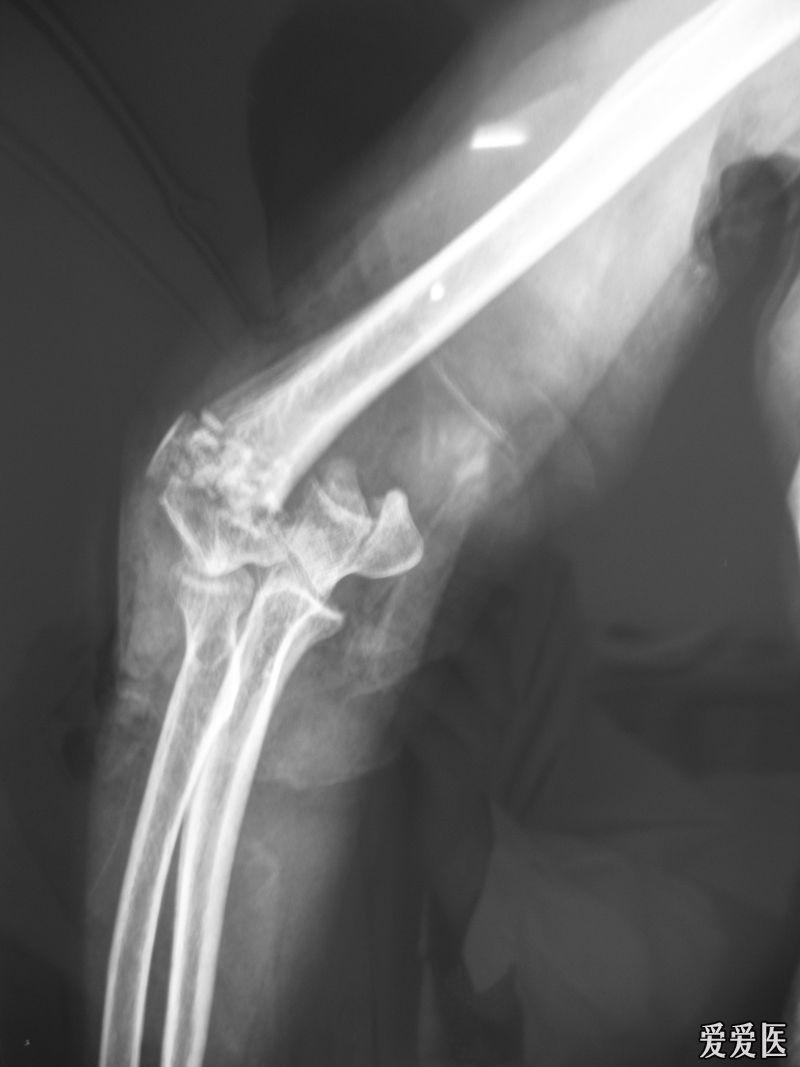

右肱骨髁间粉碎性骨折